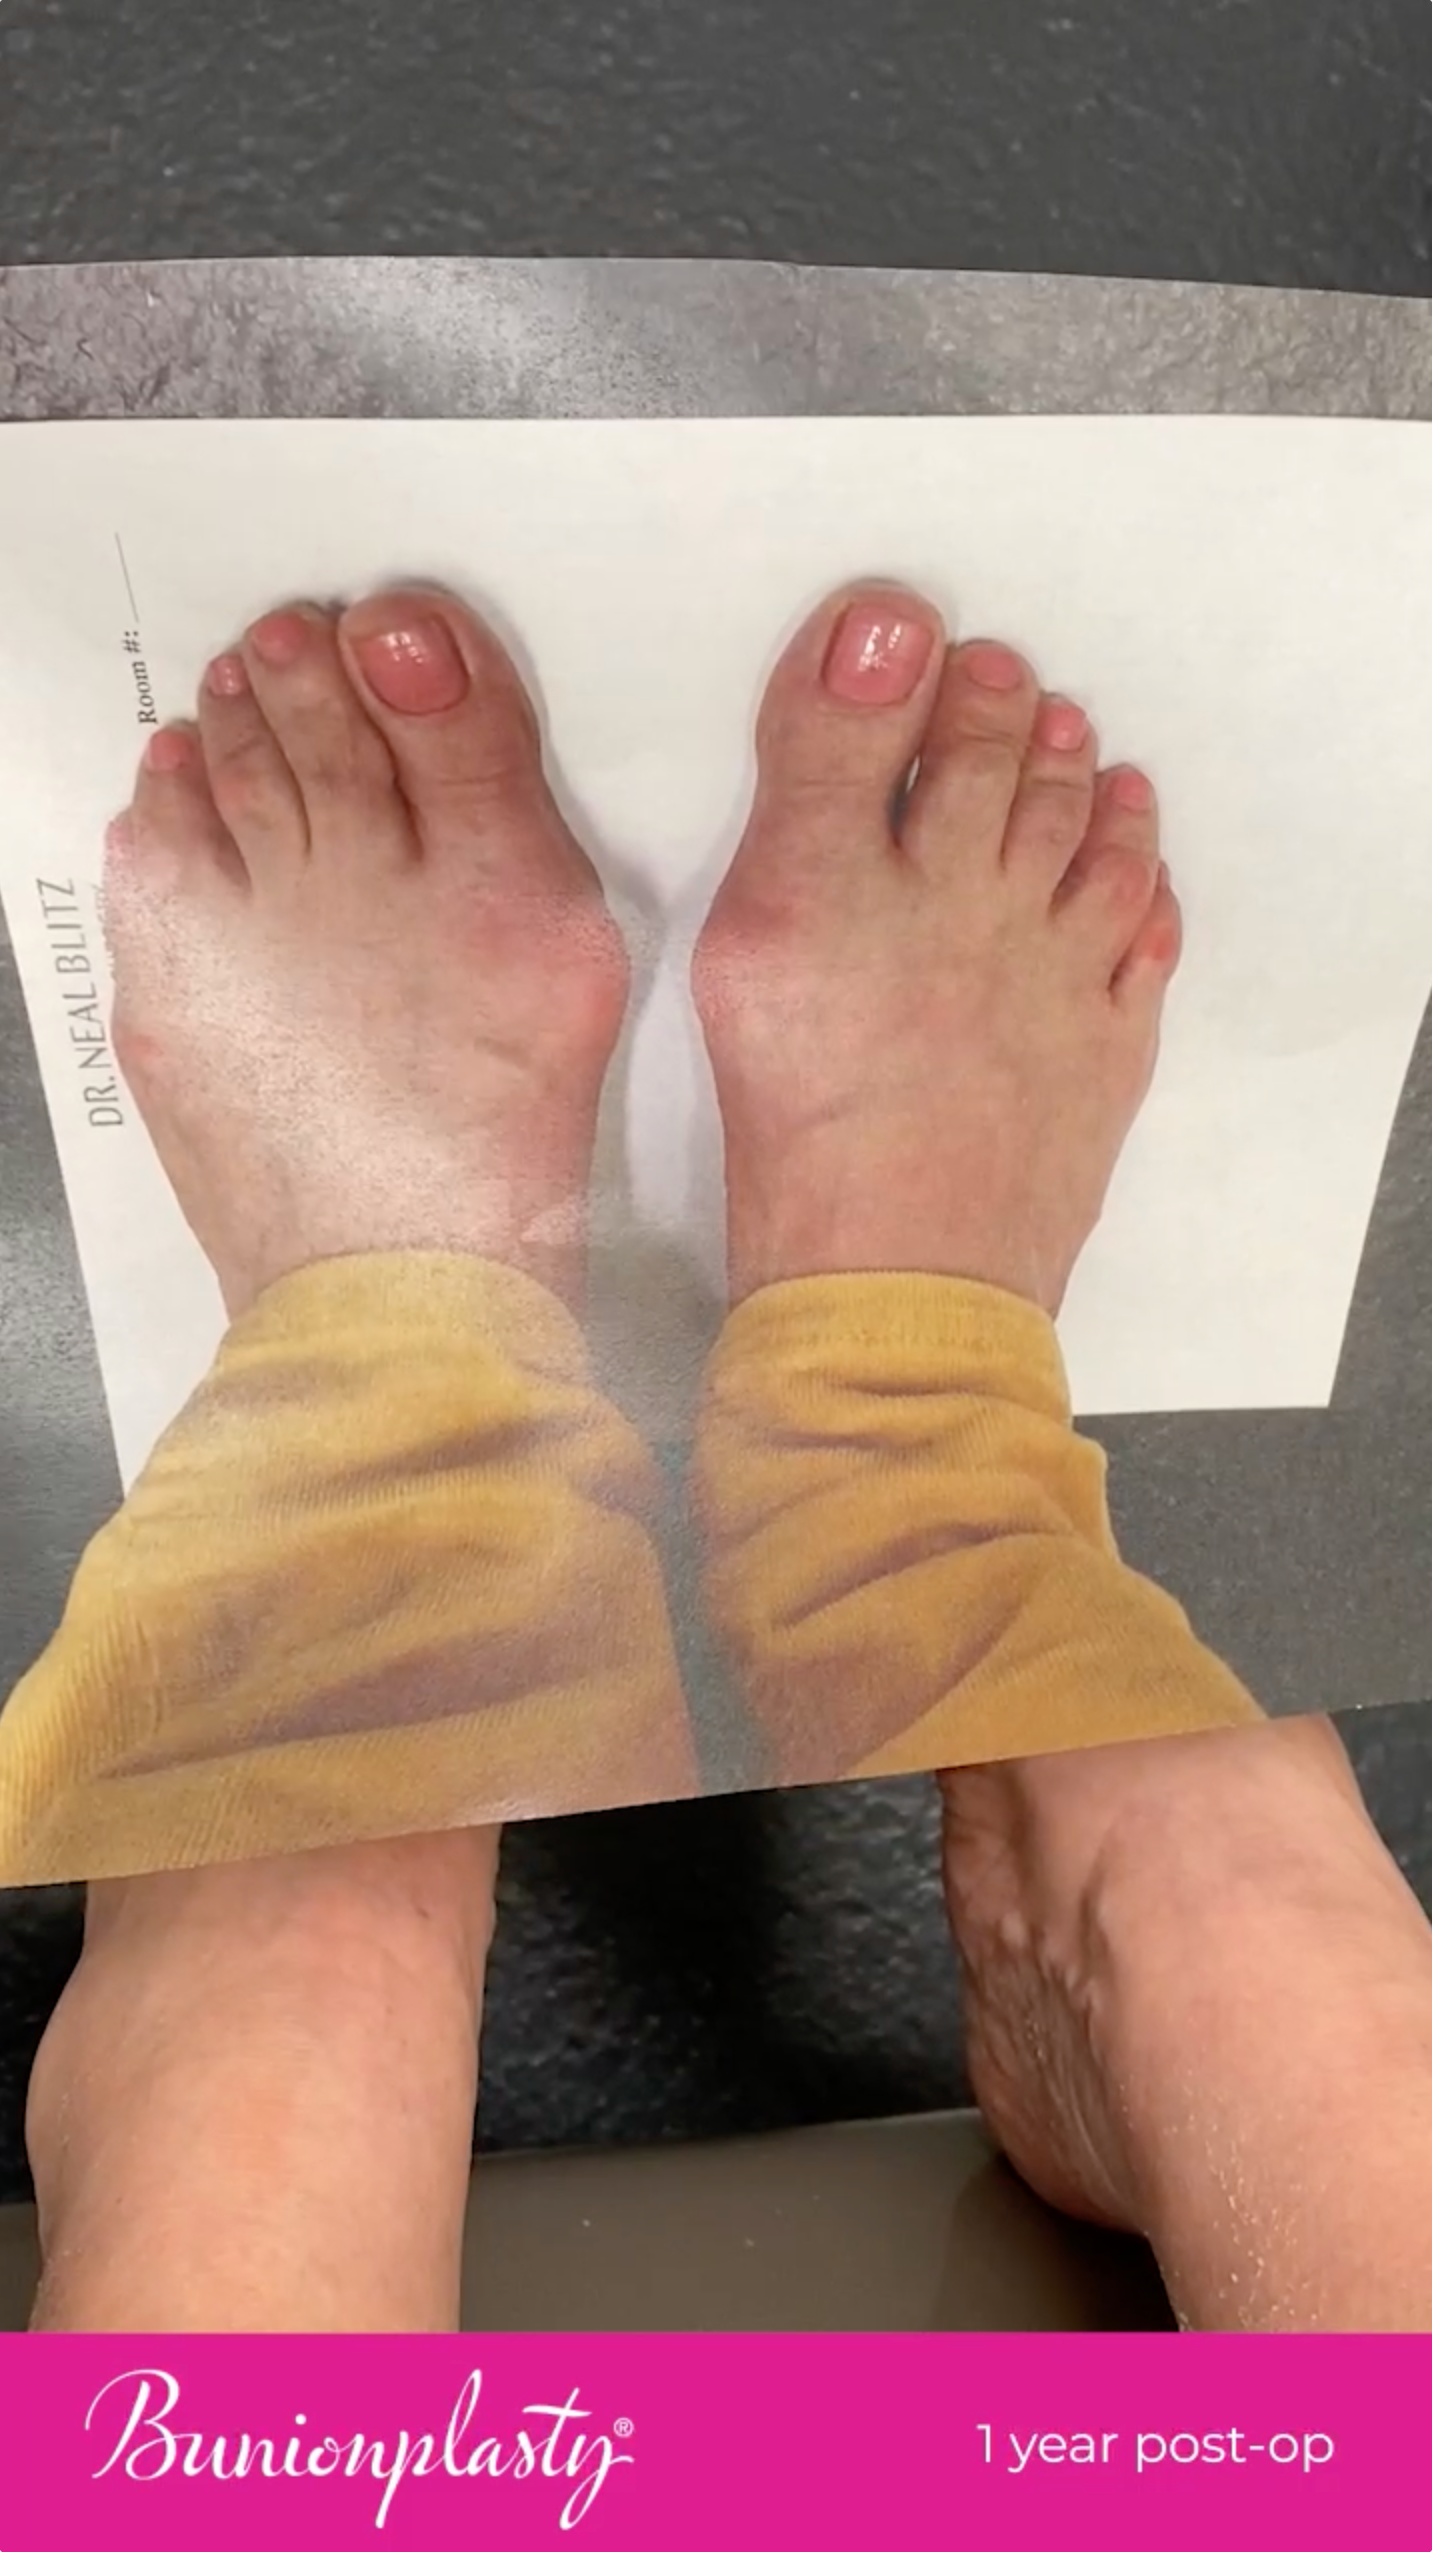

From “ow” to wow.

Real patients, real milestones, real results. Your feet could be next!

These videos depict results of the patent-pending Bunionplasty® procedure technique in real patients. A number of these procedures were performed using the patented Revcon™ minimally invasive screw system.